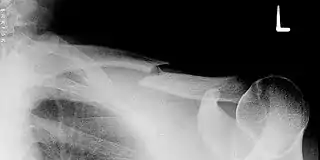

![]() Radiografía de una fractura completa de la clavícula del hombro izquierdo. | ||

Aproximadamente el 80% de las fracturas de la clavícula se producen en el tercio medio del recorrido del hueso, 15% con asociación de la parte distal o el tercio lateral, y un 5% de asociación del tercio proximal o medial.[1]